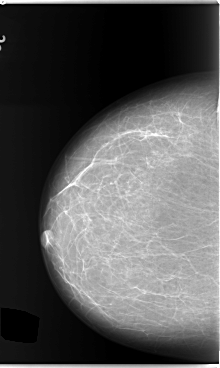

C_0132_1.LEFT_MLO

LEFT_MLO LINES 5920 PIXELS_PER_LINE 3784 BITS_PER_PIXEL 12 RESOLUTION 50 OVERLAY